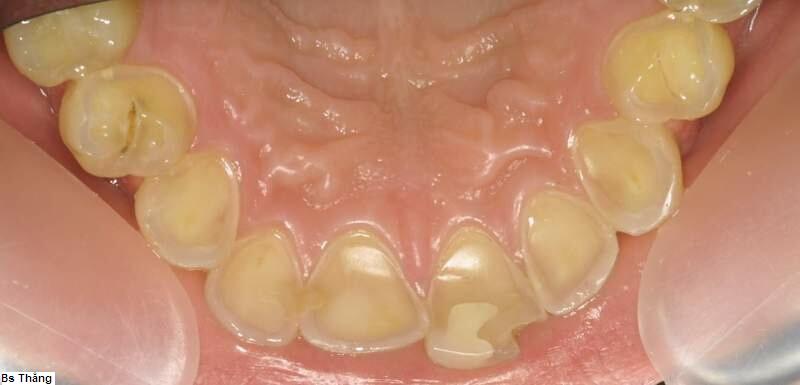

![]() ![]() | Mòn mặt trong răng do trào ngược dạ dày, thực quản |